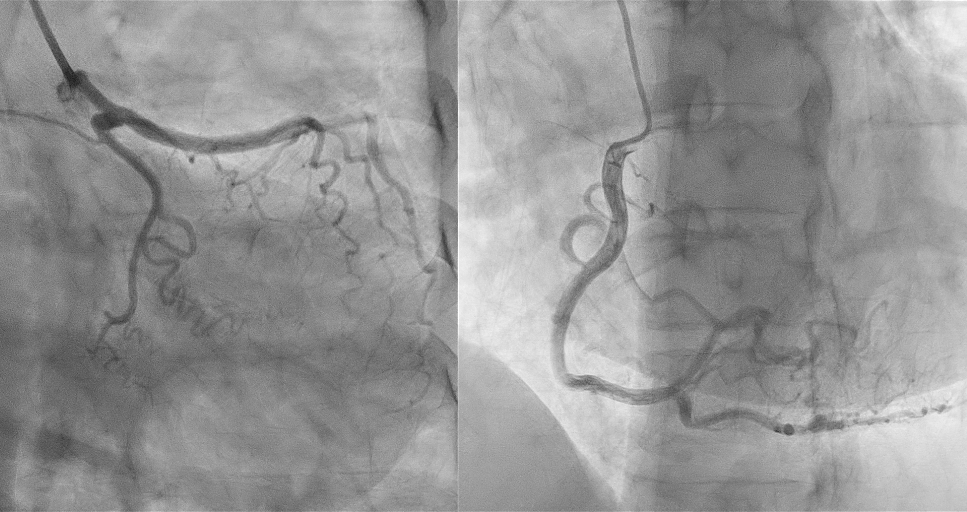

Coronary angiogram via Right radial accessLeft mainstem coronary artery (LMCA) : Moderate Disease 60% TIMI 3

IVUS pullback performed:

Dynamic compression of LMCA externally (MLA reduction by 47.3%, from 12.8 to 6.74 mm2)Minimal intimal plaqueLAD, LCX, RCA was normal.